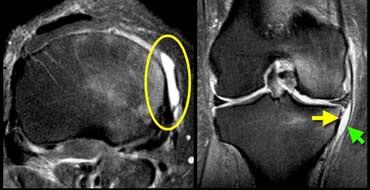

TRÁI: Rách một phần gân cơ tứ đầu đùi. Chỉ có gân cơ thẳng đùi bị rách (mũi tên xanh). PHẢI: Bệnh lý gân có từ trước (vòng tròn vàng) trên ảnh mặt phẳng ngang.

Một ví dụ khác về rách một phần gân cơ tứ đầu đùi.

Viêm xương sụn bóc tách

Chẩn đoán Viêm xương sụn bóc tách thường được thực hiện trên X-quang.

Câu hỏi đặt ra khi chụp MRI là tổn thương ổn định hay không ổn định.

Ca lâm sàng bên trái là không ổn định vì hai lý do:

– Các nang nhỏ ở nền tổn thương (mũi tên đỏ)

– Quan trọng hơn là có dịch ở nền tổn thương (mũi tên xanh)

Lưu ý rằng lớp dịch này khác với AVN, nơi dịch nằm giữa sụn và xương.

Viêm xương sụn bóc tách không ổn định. Dấu hiệu duy nhất có giá trị để chẩn đoán OD không ổn định là dịch (mũi tên vàng), không phải phù tủy hay gián đoạn bề mặt xương sụn (mũi tên xanh lá).

Các dấu hiệu không có giá trị trong việc phân biệt OD ổn định và không ổn định bao gồm:

– Phù tủy xương (có thể gặp trong cả hai trường hợp)

– Gián đoạn bề mặt xương sụn.

Vì vậy, ca lâm sàng bên trái là không ổn định vì có dịch ở nền tổn thương.